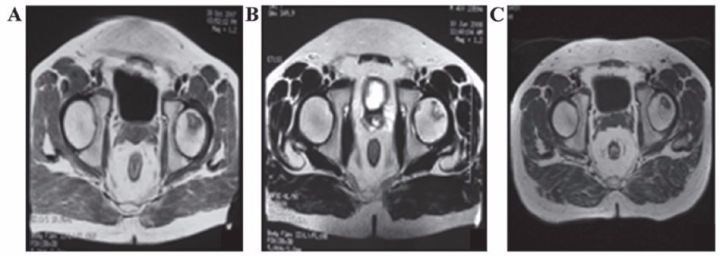

✔ 股骨头坏死

间充质干细胞移植治疗人体股骨头坏死在国外已有报道。法国科学家移植治疗116例股骨头坏死患者效果显著,其中87.3%的患者髋关节疼痛缓解;78.4%的患者关节功能改善;80%的患者行走间距延长。

吉林一位许姓小伙在一次攀岩活动中从高处摔下来,送到医院检查,双侧股骨头已坏死变形。按照常规治疗方法,应行人工关节置换手术。可是人造股骨头的寿命一般在10-15年,小许才27岁,一辈子需要不停地更换人工关节。

沈阳463医院的杨晓凤主任将间充质干细胞经过技术处理后注入小许的股骨头,两周后小许就可以下地行走了。10个月后,小许来医院复查,他的股骨头周围已长出丰富的血管,表明移植的间充质干细胞促使坏死变性的股骨头修复新生。

表8 刘颖、谷涌泉应用脐带MSC治疗股骨头坏死的临床研究结果

吉林省组织工程重点实验室刘颖教授 、首都医科大学宣武医院谷涌泉主任等,对9位骨循环协会评级为II-IIIa级的股骨头坏死患者经大腿动脉输注脐带间充质干细胞后,患者的红细胞、血小板、血氧转运指数明显改善。MRI检测显示24个月后股骨头坏死区域体积显著减少。